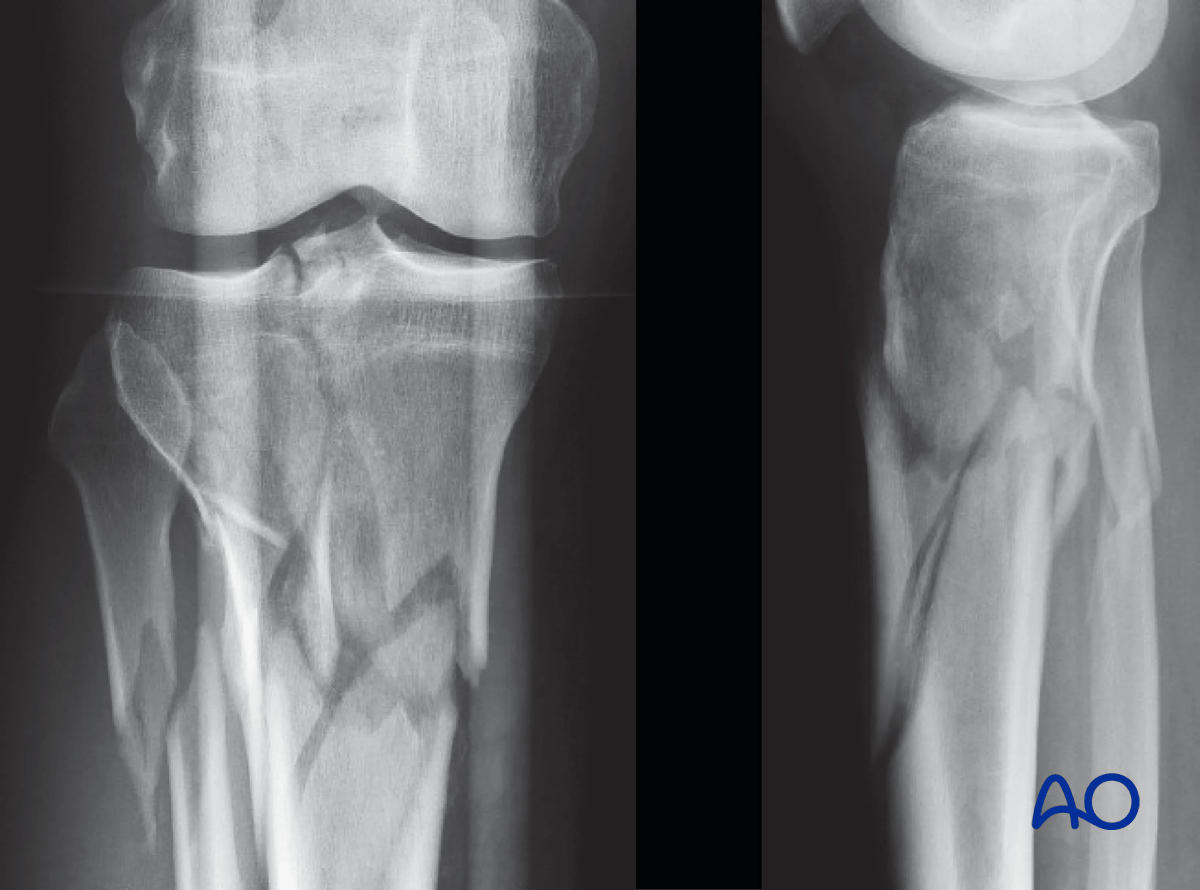

9. Case example

The clinical case shows a 45-year-old man injured in a motorcycle accident, sustaining a closed injury of his proximal tibia of the type 41.C2.2. Initial treatment consisted of placement of a temporary spanning frame and CT scanning for preoperative planning. Forty-eight hours later definitive fixation was performed.

Proximal tibia fracture – a closed injury of the type 41.C2.2